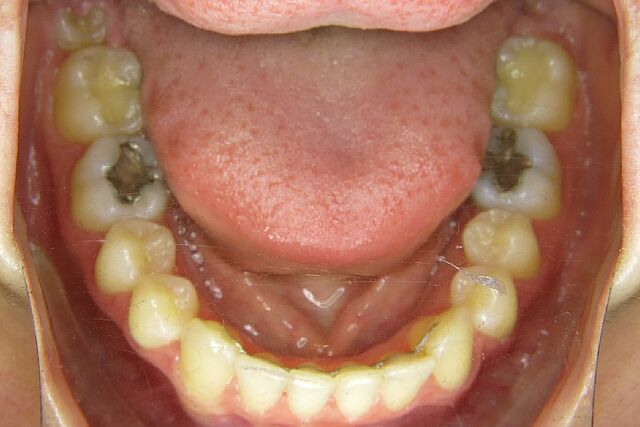

Jasmin wurde in nur 14 Monaten mit einer festsitzenden Zahnspange mit durchsichtigen Brackets behandelt.

• Engstand

• Kreuzbiss

• Scherenbiss